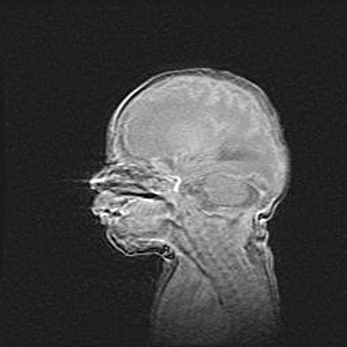

Церебральная ишемия II.

Возраст: 5 дней

Вес: 3400 г

Пол: женский

Окружность головы: 35 см

Срок гестации: 39 недель

Церебральная ишемия – это заболевание, характеризующееся недостаточностью (гипоксией) либо полным прекращением (аноксией) снабжения мозга кислородом по причине закупорки одного или нескольких сосудов. Это приводит к  что метаболическим расстройствам различной степени тяжести в тканях головного мозга, развитию коагуляционных некрозов и гибели нейронов.